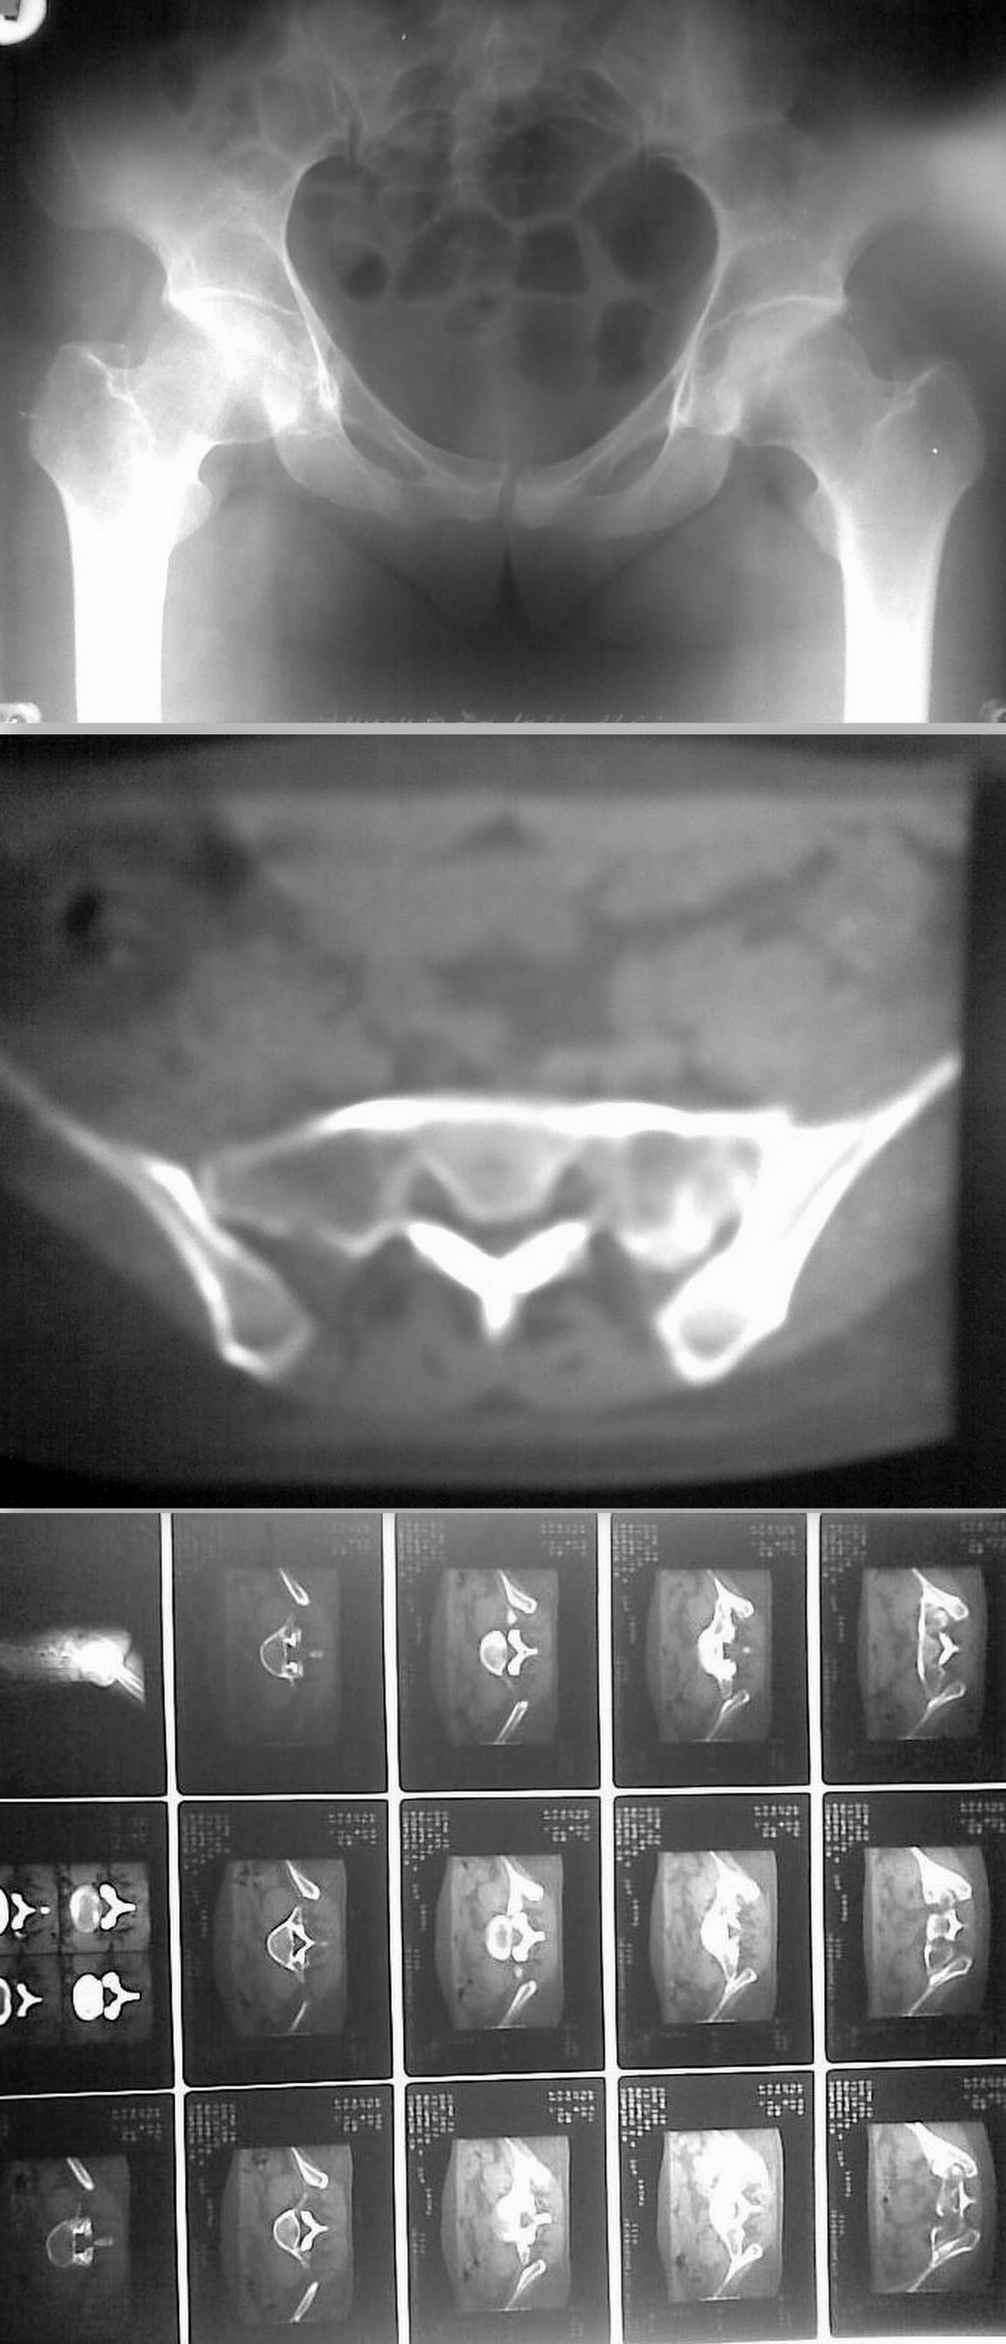

Больная 32 лет поступила в отделение 02.03.10. Травма 26.12.09 ДТП в качестве пассажира (сидела сзади, машина перевернулась). Находилась на амбулаторном(?)лечении с диагнозом "перелом седалищной кости справа". Через 2 месяца после травмы больная вертикализирована, но отмечались интенсивные боли в поясничном отделе с иррадиацией по задней поверхности бедра. Больная направлена в стационар. Выполнена КТ. Картина в приложении.